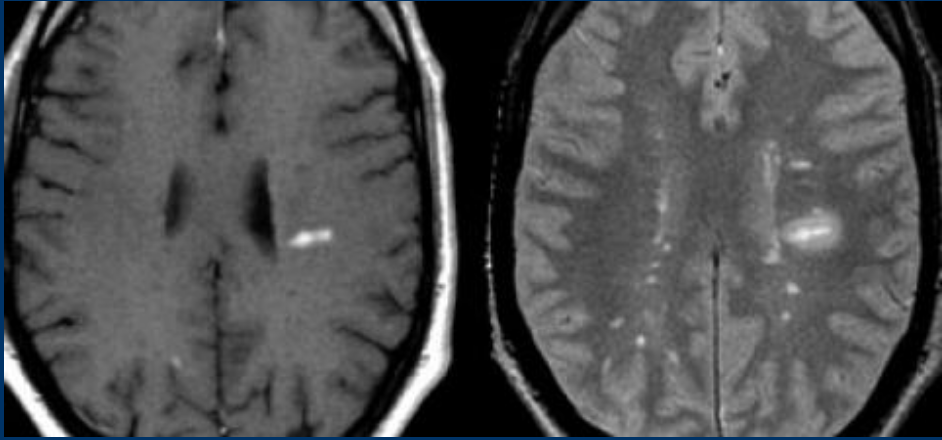

Exames de Imagem

incluir as imagens e as caracteristicas de em